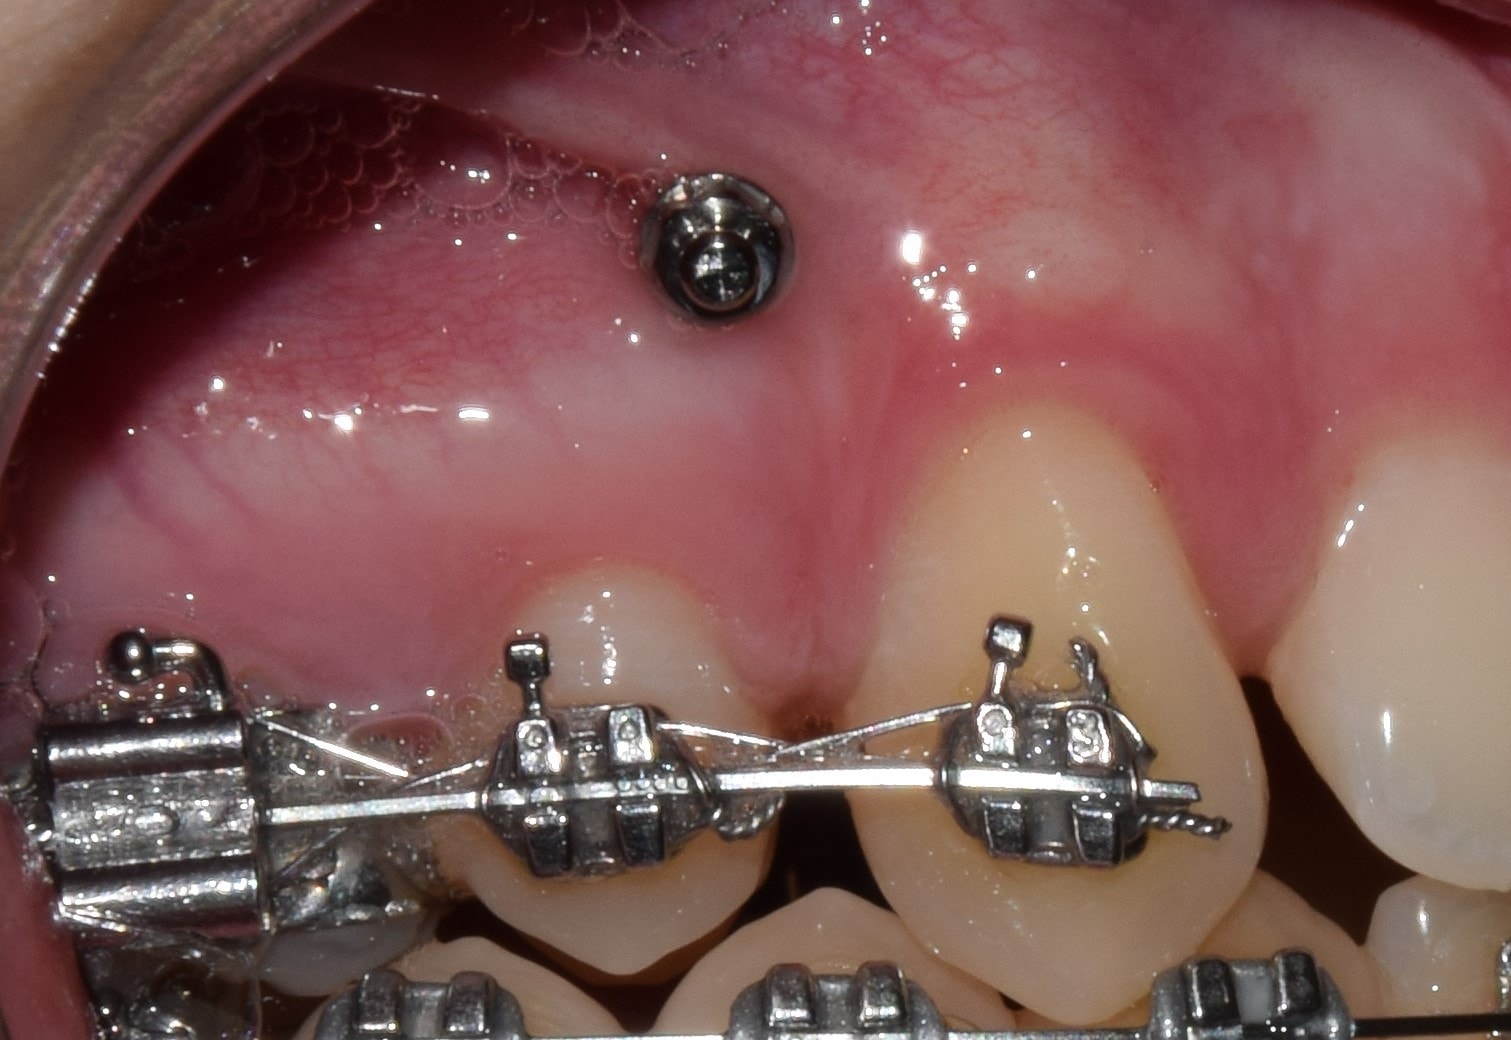

Fogszabályozási miniimplantátum

A modern fogszabályozó kezelések alappillérei a fogszabályozási miniimplantátumok. Óriási előnyökkel jár használatuk, és a kezelések sikerességét hihetetlen mértékben megnövelik. Miniimplantátumok segítségével a korábban csak műtéttel, foghúzással kezelhető pácienseket egyszerű fogszabályozással is tökéletesen kezelni tudjuk! Az önligírozó fogszabályozó rendszerek és miniimplantátumok kombinált használata talán a legsikeresebb technikát jelenti jelenleg. Nagyon minimális helyi érzéstelenítésben történik behelyezésük, mely nagyjából 20-40 másodpercet vesz igénybe! Az injekciót leszámítva teljesen fájdalommentes beavatkozás! A fogszabályozási miniimplantátumok a fogászati implantátumokkal szemben nem kerülnek szoros kapcsolatba a környező szövetekkel, ezáltal későbbi eltávolításuk igazán egyszerű, érzéstelenítő sem szükséges hozzá. Technika- és szájhigiéné érzékeny rendszerről beszélünk. Nem megfelelő fogmosás következményeként a minicsavarok meglazulhatnak, kieshetnek.

Behelyezési területük szerint három fő csoportot különböztetünk meg:

1. A gyökerek közé helyezett miniimplantátumok

Ezeket a miniimplantátumokat a fogak gyökerére merőlegesen helyezzük be, a gyökerek közé. Pontos helyzetüket előzetes kisröntgen alapján határozzuk meg. Ezekkel végezzük a foghiányok zárását, bizonyos fogak pozícióban tartását, elülső fogak felfelé/lefelé mozgatását stb.